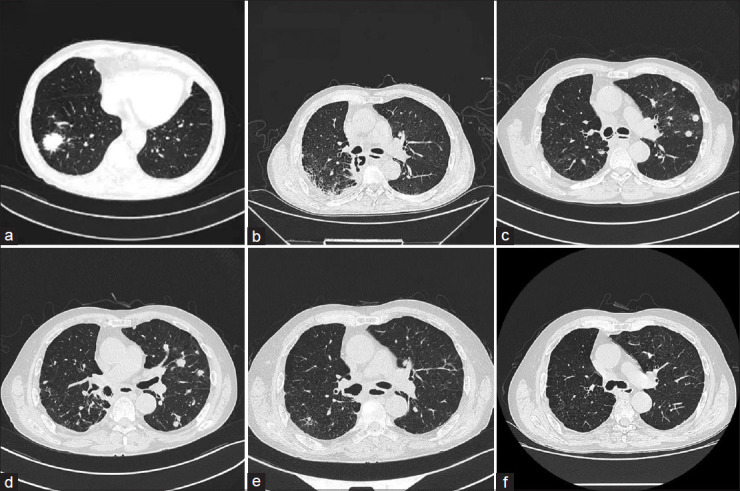

Bronchopleural fistula (BPF) is a rare yet severe complication following lobectomy, with no standardized treatment protocol established. We present a case of a 65-year-old male with chronic obstructive pulmonary disease who developed multiple BPFs postresection of the right lower lobe due to lung cancer and with tumor recurrence and metastasis. We employed a comprehensive management strategy comprising rigorous infection control, meticulous chest drainage, antitumor treatment, and targeted deployment of bronchial stents. This approach not only resolved the BPFs but also achieved a complete response of the lung cancer, extending progression-free survival to over 3 years.